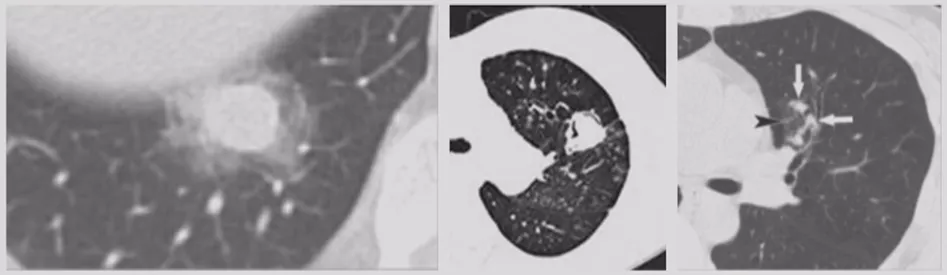

内部特征:燕麦圈征(开放支气管征)

还有非常容易被大家忽略的一个特点(如上图所示),文献上把这个病灶称为燕麦圈征,这不是个好征象。由开放气道周围的肿瘤细胞或非肿瘤细胞增生所致,多见于肺腺癌和肺朗格汉斯细胞组织细胞增多症。尤其是女性病人出现这种征象的概率比较高,出现之后一定要手术。